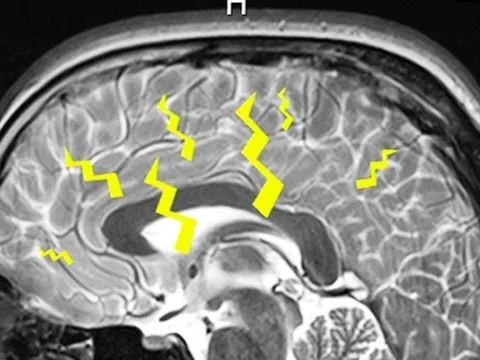

Dreaming remains one of biology’s biggest mysteries because dreams are hard to measure, hard to verify, and largely forgotten—an estimated 95% vanish within the first 10 minutes. Yet researchers have found a reliable window into what’s happening inside the brain. In 1952, scientists at the University of Chicago identified a distinct pattern of electrical activity tied to a particular sleep stage: when people were awakened during that stage, they almost always reported dreaming. At the same time, their eyes moved rapidly beneath their eyelids—an outward sign of the same internal state.

That stage is REM sleep, where the brain’s electrical behavior closely resembles wakefulness, but key chemical signals—norepinephrine, serotonin, and histamine—are largely blocked. The result is a mismatch between mind and body: the brain can generate vivid scenarios (flying, running, fighting) while muscle activity is suppressed, preventing the body from acting them out. This suppression can fail in disorders involving “achieving complete REM atonia,” where people may move, get out of bed, or sleepwalk while still experiencing dream content.